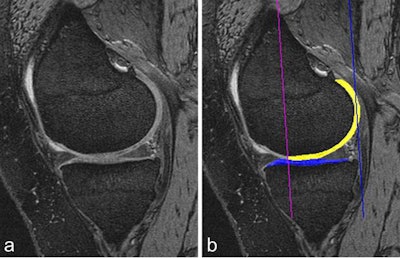

For quantitative and qualitative analyses using MRI, Roemer finds 3D morphometry particularly valuable.

"This is based on tissue segmentation and is being widely used for cartilage quantification," he said. "The cartilage tissue is well contrasted between the intra-articular fluid and the subchondral bone. Regions of interests are drawn around the cartilage, and multiple parameters can be extracted from those 3D segmentations, including cartilage volume, cartilage thickness, the amount of the denoted bone area beneath the cartilage, and so on."

Compositional MRI techniques, including T2 mapping or T2 relaxometry, can be used to look at the ultrastructure of tissue. Basically, the different analytical approaches are semiquantitative, quantitative, and qualitative compositional measures of tissue change, Roemer noted.